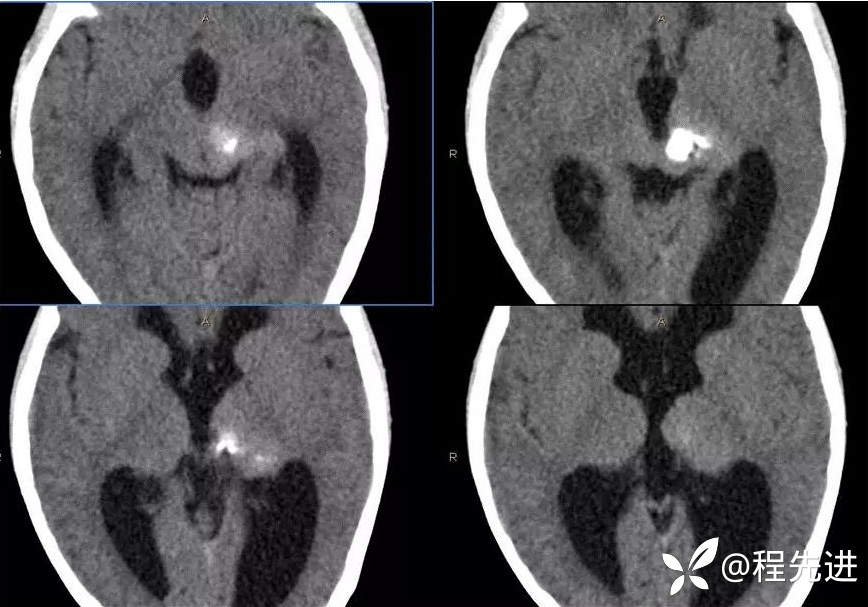

CT